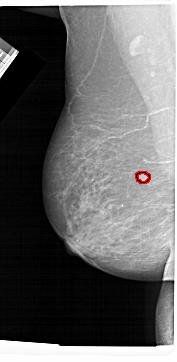

A_1481_1.LEFT_CC

LEFT_CC LINES 6256 PIXELS_PER_LINE 2956 BITS_PER_PIXEL 12 RESOLUTION 43.5 OVERLAY

FILE: A_1481_1.LEFT_CC.OVERLAY

TOTAL_ABNORMALITIES 1

ABNORMALITY 1

LESION_TYPE MASS SHAPE ROUND MARGINS CIRCUMSCRIBED

ASSESSMENT 3

SUBTLETY 4

PATHOLOGY BENIGN

TOTAL_OUTLINES 1

BOUNDARY